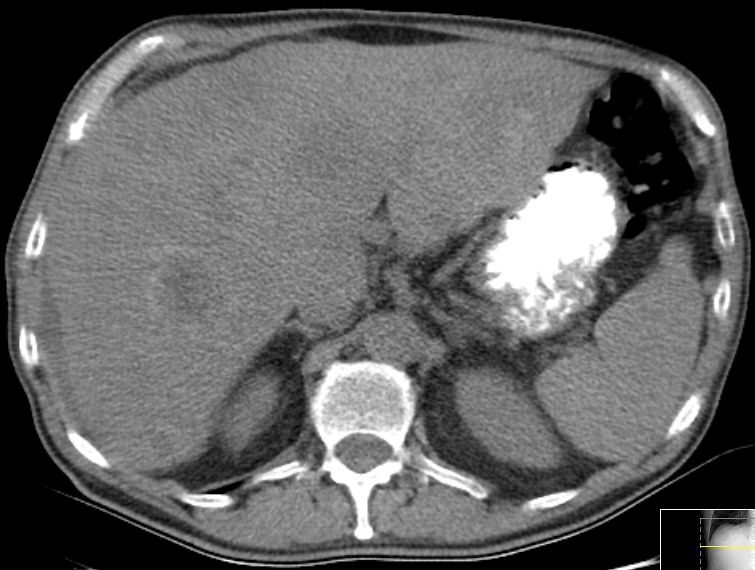

39-jährige Frau mit einem primär hepatisch metastasierten Transversum-Karzinom. Histologisch gering differenziertes Adenokarzinom ras-Wildtyp. Das CT zeigt eine große Metastase im rechten Leberlappen und eine Metastase im Lobus caudatus. Letztere ist schwer zu resezierten und sollte in einem Zentrum operiert werden.